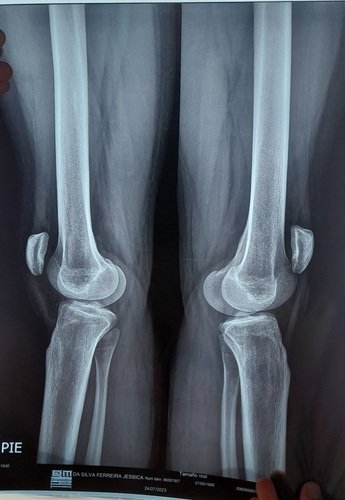

Meu nome é Jessica e tenho 24 anos, desde pequena sinto muitas dores nas pernas e os médicos diziam que era dor de crescimento, e até reumatismo e a dor foi só aumentando até que a rotula do joelho começou a sair do lugar, fiz alguns exames e descubri que tenho displasia rotuliana tipo c e condromalacia grau 4( não há mais cartilagem nos 2 joelhos) e com o passar dos anos foi piorando e agravando também a tibia.